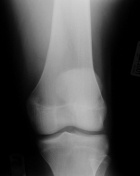

D.O. - 14 year old male with one year hx of left knee pain.

Zoom image: Radiological image Radiological image.